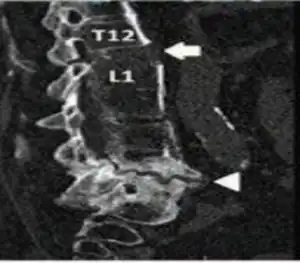

Inadequately healed chalk stick fracture with sclerotic margins was seen at L4-L5 level arrow head